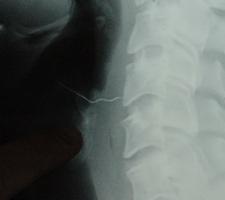

Nurol Güral (27) bir lokantada yemeğini yedikten sonra sütlacı yemeye başladı. Güral, fark etmeden sütlacın içinde bulunduğunu iddia ettiği 4 cm boyundaki çelik teli sütlaçla birlikte ağzına aldı. Tel midesine inmeden Güral'ın boğazına saplandı. Zor anlar yaşayan Güral özel bir hastaneye kaldırıldı. Tel burada çıkarılamadığı için Güral, Trabzon'da bulunan Karadeniz Teknik Üniversitesi (KTÜ) Farabi Hastanesi'ne sevk edildi. Burada yapılan cerrahi müdahalenin ardından tel boğazından çıkarıldı. Güral,

tedavinin ardından olayla ilgili lokantanın sahiplerinden davacı oldu.